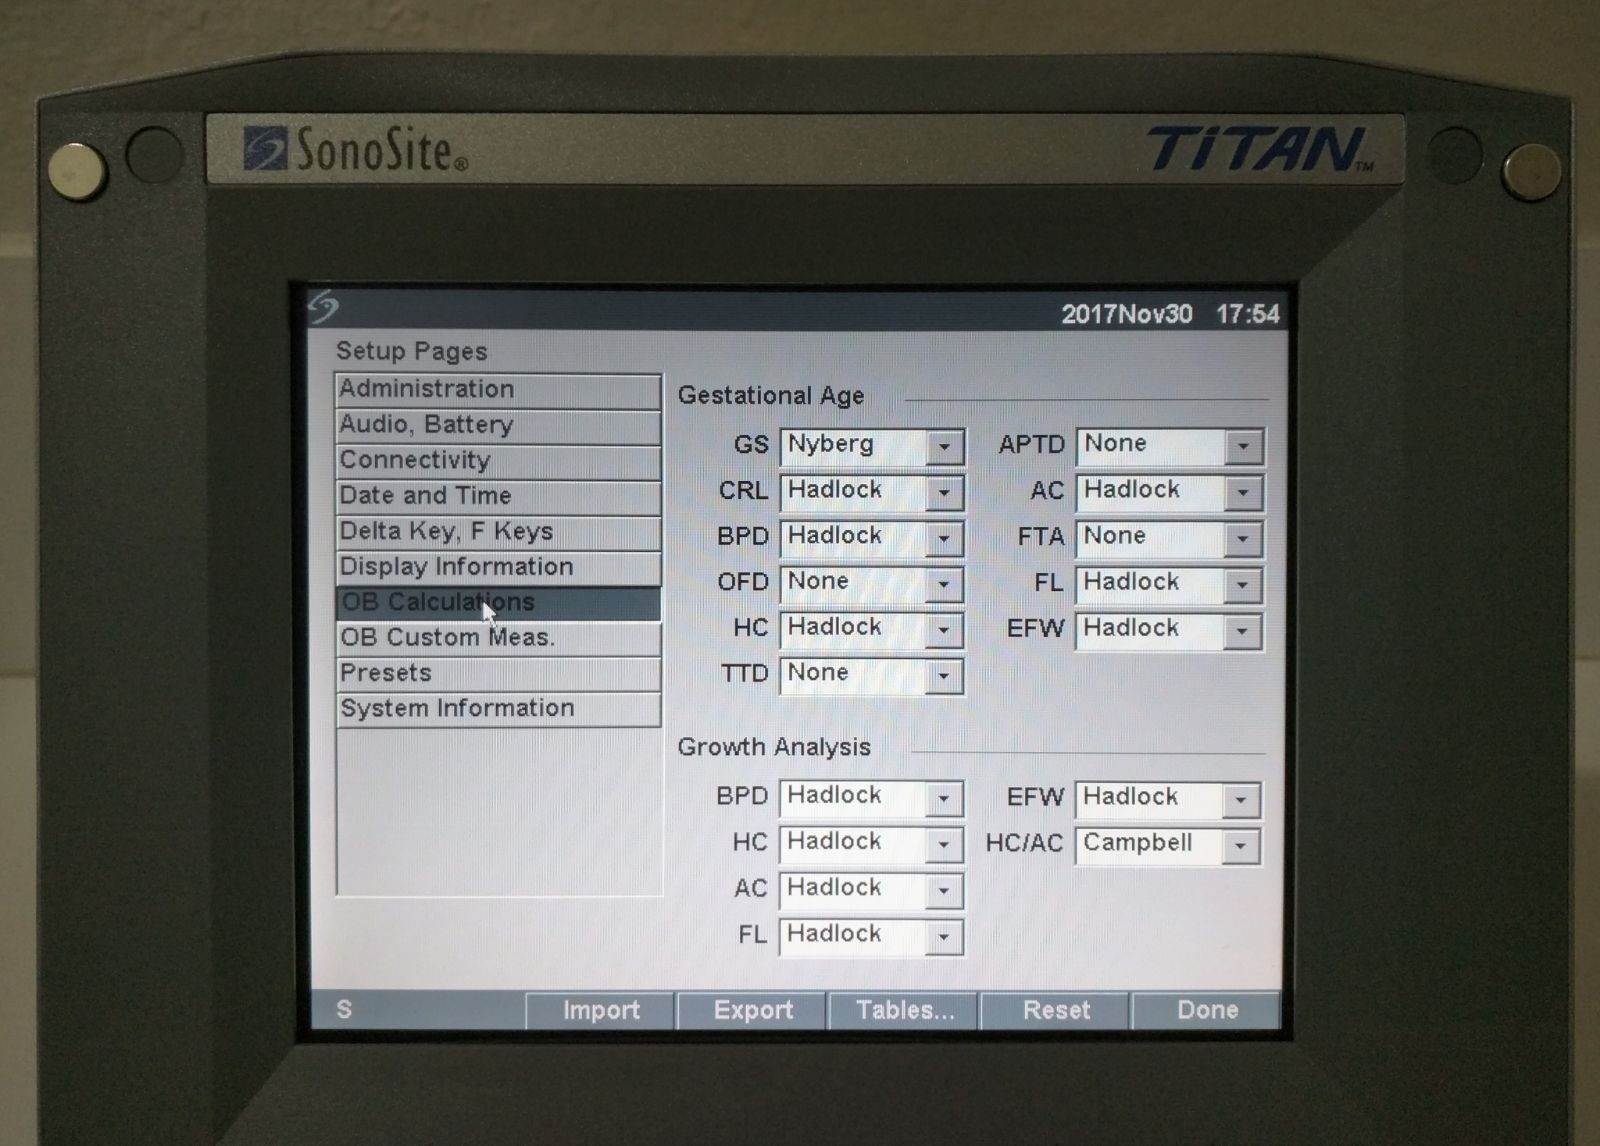

The SONOSITE TITAN OB/GYN ultrasound offers state-of-the-art imaging technology. This device uses advanced algorithms to provide clear, high-resolution images. It includes two probes: a 1-C60 convex and a 1-ICT transvaginal probe, ensuring versatility in different obstetric and gynecological applications. Because of its compact design, the SONOSITE TITAN is perfect for both hospital and remote settings, making it an ideal choice for healthcare providers.